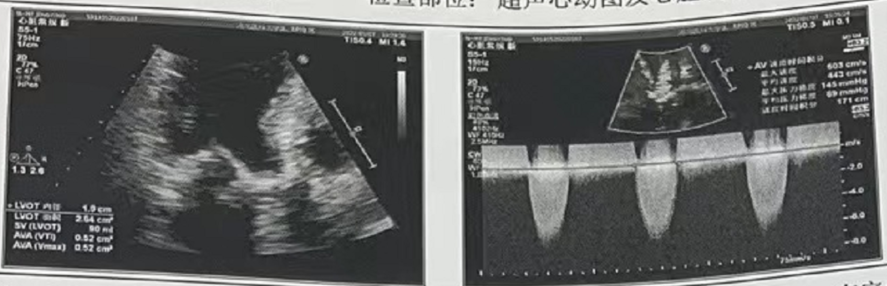

心脏彩超

峰值流速:4.9M/s

最高跨瓣压差:98mmHg

平均跨瓣压差:50mmHg

左室射血分数EF值:0.48

左室舒张末期内径(LVD):5.39 cm

主动脉瓣评估:主动脉瓣二叶瓣(TypeⅠ) 主动脉瓣重度狭窄,轻度反流。左室壁肥厚,二三尖瓣轻度反流,左室舒张功能减低。

主动脉瓣瓣叶显著增厚钙化;

瓣叶交接处粘连;

收缩期峰值流速603cm;

峰值压差145mmHg;平均压差89mmHg;

连续方程法瓣口面积 0.5cm2;

主动脉瓣关闭不良,舒张期中量反流。

超声提示:

主动脉瓣重度狭窄,中度反流,左室壁肥厚,左房增大, 二、三尖瓣轻度反流。